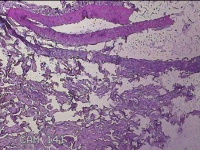

右侧颈部包块

性别

男

年龄

32岁

临床诊断

皮下结节

一般病史

发现右侧颈部包块3年余。

标本名称

大体所见

灰白暗红色包块1.5x1.3x0.7cm,表面光滑,切面灰白暗红色,质软。

图2

良性病变。